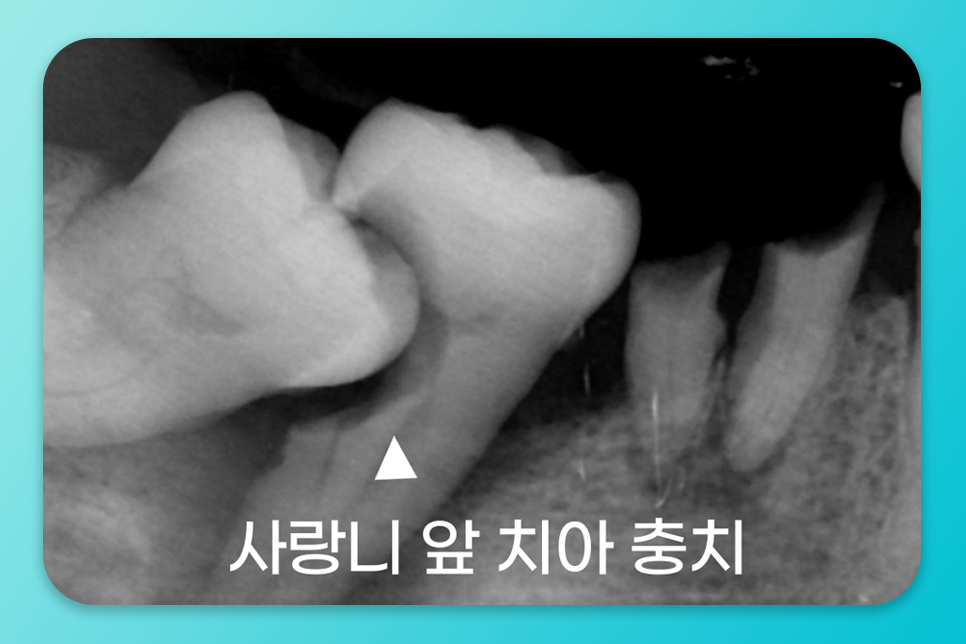

만약, 방치되어 충치나 염증이 악화된다면

앞 어금니까지 손상될 수 있어

주의하셔야 합니다.

앞 어금니에 음식 끼임, 충치 위험을

높이는 위치라면